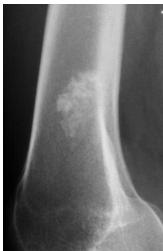

Popcorn, cartilaginous - chondrosarcoma usually - even though theres no perosteal reaction

site: distal femur size: Most (involving how much? / cm?) matrix: mixed - mainly radiopaque , wide zone of transition, cortical destruction, resulted periosteal reaction, and codman’s triangle soft tissue involvement: